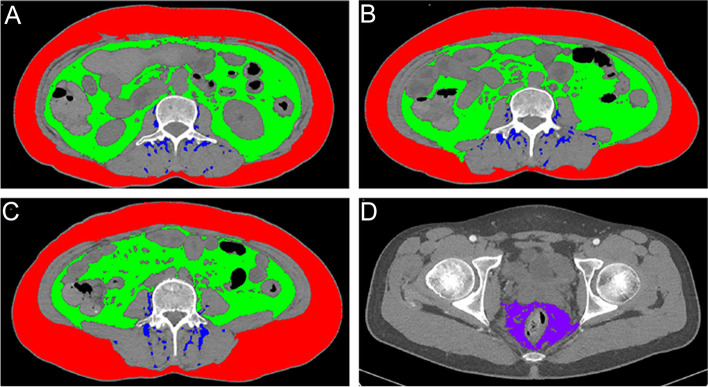

Measurement strategies should be tailored to accommodate the physiological and anatomical characteristics of different adipose compartments. A cross-sectional measurement of subcutaneous, visceral, or paraspinal intramuscular adipose tissue at the third lumbar vertebra accurately reflects whole-body fat mass [21, 22], which is less stable due to individual variations and errors in slice selection. Therefore, they were recorded at the second to fourth spinal levels and integrated. The tip of the ischial spines was chosen as a bony landmark to quantify mesorectal adipose tissue [23]. The SliceOmatic 5.0 software (Tomovision, Montréal, Canada) processed all scans and automatically computed the horizontal areas of adipose tissue compartments based on Hounsfield unit values. We traced the boundaries of adiposity regions and corrected the segmented bias in each slice. Adipose tissue zones are illustrated in Fig. 2. To standardize the estimated areas, they were normalized by dividing with the square of the height and expressed in cm2/m2, further producing subcutaneous adipose tissue index (SATI), visceral adipose tissue index (VATI), paraspinal intramuscular adipose tissue index (PSAI), and mesorectal adipose tissue index (MATI). We have calculated the mesenteric fat index (MFI), which denotes the ratio of visceral fat area and subcutaneous fat area [14].

Fig. 2.

Diagram of the human fat compartments. A–C. Subcutaneous, visceral, and paraspinal intramuscular fat areas were measured at L2, L3, and L4. D. Mesorectal fat measured at the tip of the ischial spines. Subcutaneous fat is shown in red, while green and blue represent visceral and paraspinal intramuscular fat. L2, second lumbar vertebra; L3, third lumbar vertebra; L4, fourth lumbar vertebra